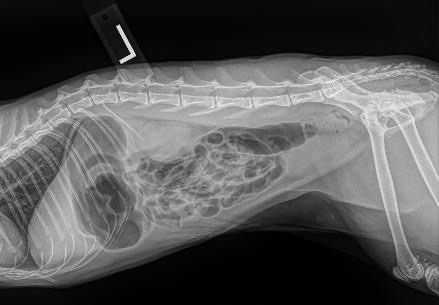

As many know, my pets are like my children. Zoey, my Sphynx cat, may have a small bowel obstruction and might require surgery. She began to not eat for a day and a half, also showing signs of nausea by gagging. I always take every precaution that there is. I have elevated bowls for all my cats. Zoey gets high-quality food. They get probiotics for their teeth. But in this case, I don’t know why this happened. Zoey is required to stay overnight in the ER for fluids and 12 hours of observation. Please, anything helps. I love her so much and I wouldn’t want to lose her.